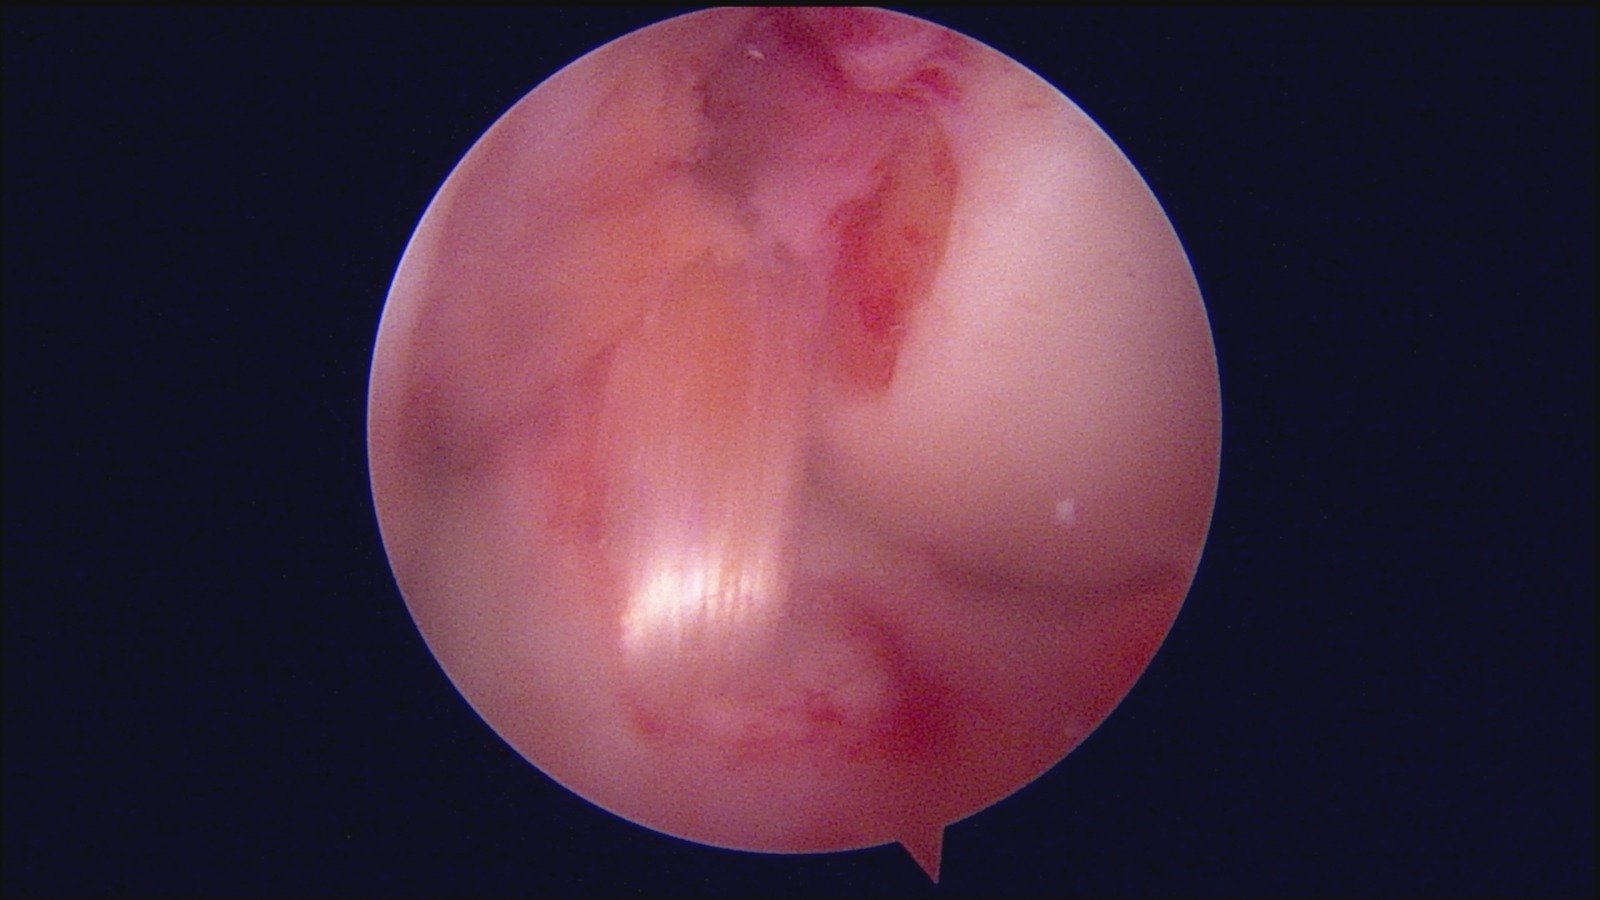

GalleryShoulder rotator cuff repair Meniscus root repair Meniscus repair Bankart repair for recurrent shoulder dislocation ACL reconstruction Machines Instruments